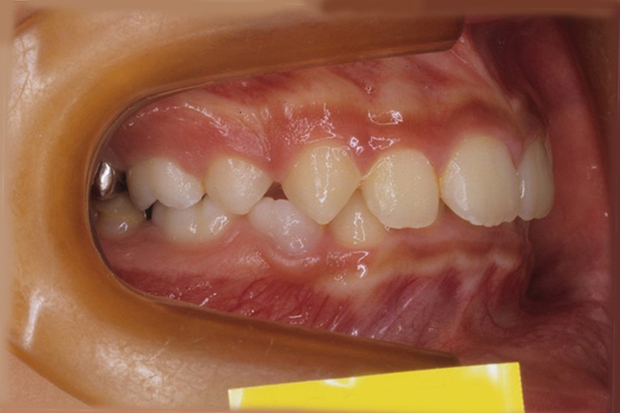

【ハーフリンガル】叢生 抜歯 上顎舌側マルチブラケット装置

| 主訴 |

ガタガタ |

||

|---|---|---|---|

| 診断名 |

右側Angle II級叢生 |

||

| 年齢 | 19歳 | 性別 | 女性 |

| 治療に用 いた装置 |

ハーフリンガル装置 (セミカスタム) | 抜歯部位 | 上顎両側第一小臼歯 下顎両側第二小臼歯 |

| 治療期間 ・回数 |

2年・24回 | 治療費 概算 |

約85万円 (調整料を含む) |

| 治療内容 詳細 |

歯科衛生科に入学し、自分の歯ならびが気になり始めたとのこと。上の歯列のみ舌側矯正(裏側矯正)、下は表側の、ハーフリンガルで治療を行いました。 |

||

| リスク・ 副作用 |

装置による違和感。疼痛、歯根吸収など |

||